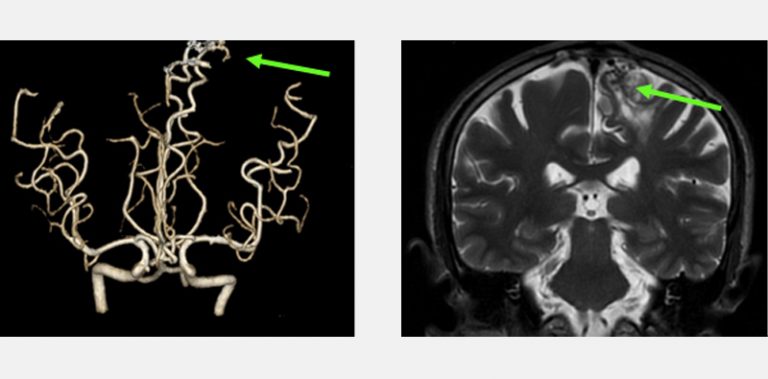

兩位分別是16歲的少年和56歲的男士,在沒有任何徵象之下做了詳盡的身體檢查,三維立體腦血管造影顯示兩人的大腦都有先天性的腦血管動靜脈畸形,在專科醫生建議之下透過了一段時間的觀察和保守治療,其後利用了微創內血管治療加上放射治療,畸形血管得到了有效的根治,病人與生俱來的大腦炸彈得到了拆除,減低了他們將來出血性中風的可能性。

三維立體腦血管造影顯示左邊大腦都有先天性的腦血管動靜脈畸